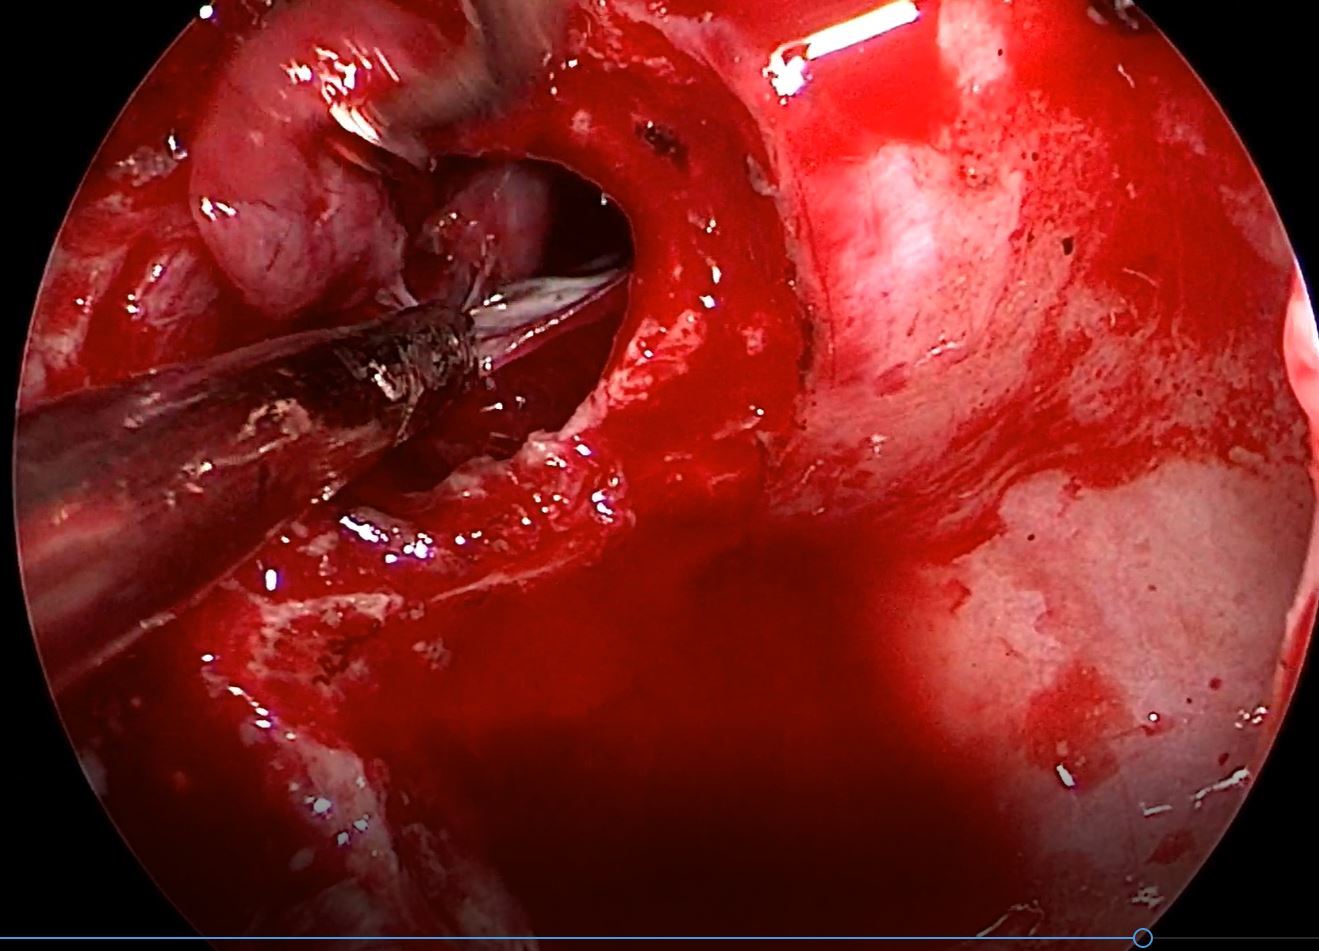

分享复发垂体瘤手术一例(原创)

图片尺寸4032x3024